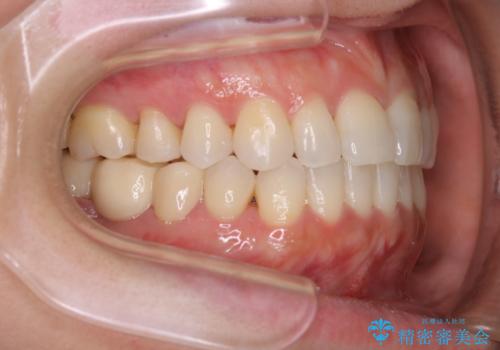

早い安いきれい!インビザラインライトで前歯のでこぼこ、反対咬合をなおす

- 前歯のがたつきと反対咬合を主訴に来院されました。

インビザライン・クリンチェック(歯のシミュレーション)を行い、

インビザラインライトで治せる範囲であることを確認し治療を開始することになりました。

今回はクリンチェックを作成したのちに、枚数が少なくても可能であることが判明したためインビザラインライトでの治療を行いました。

最初はインビザラインモデレートパッケージの予定で契約をされていたので、金額も10万円以上安くなり仕上がりも満足頂きました。